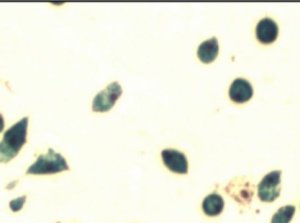

Labeling and tracking stem cells. Numerous studies have shown stem cells grown in the lab function more like normal stem cells the closer the lab environment comes to mimicking the natural environment where the cells would grow in the body. Using that strategy a team at Carnegie Mellon University in Pittsburg succeeded in loading stem cells with an FDA-approved iron nanoparticle that will allow them to track the cells after transplant.

MSCs labeled with iron nanoparticles

They focused on a type of stem cell found in bone marrow, mesenchymal stem cells (MSCs), which are being used in more than half of the 600+ active stem cell clinical trials. To date, MSC trials have produced a very mixed bag of results, with much of the poorer outcomes attributed to the cells not going to, and staying, where they are needed. So this tracking technique could help develop strategies to improve those outcomes.

Up to this point, researchers could not get the tracking agent into cells without using an agent to help get the particles across the cell membrane and those agents tend to disrupt the normal cell function. But, in their normal environment cells will engulf small particles on their own. So the Carnegie team added other cells types found in bone marrow to their lab cultures, the MSCs felt more at home, and took up the nanoparticles. A neat little trick written up in a university press release posted at Science Daily.